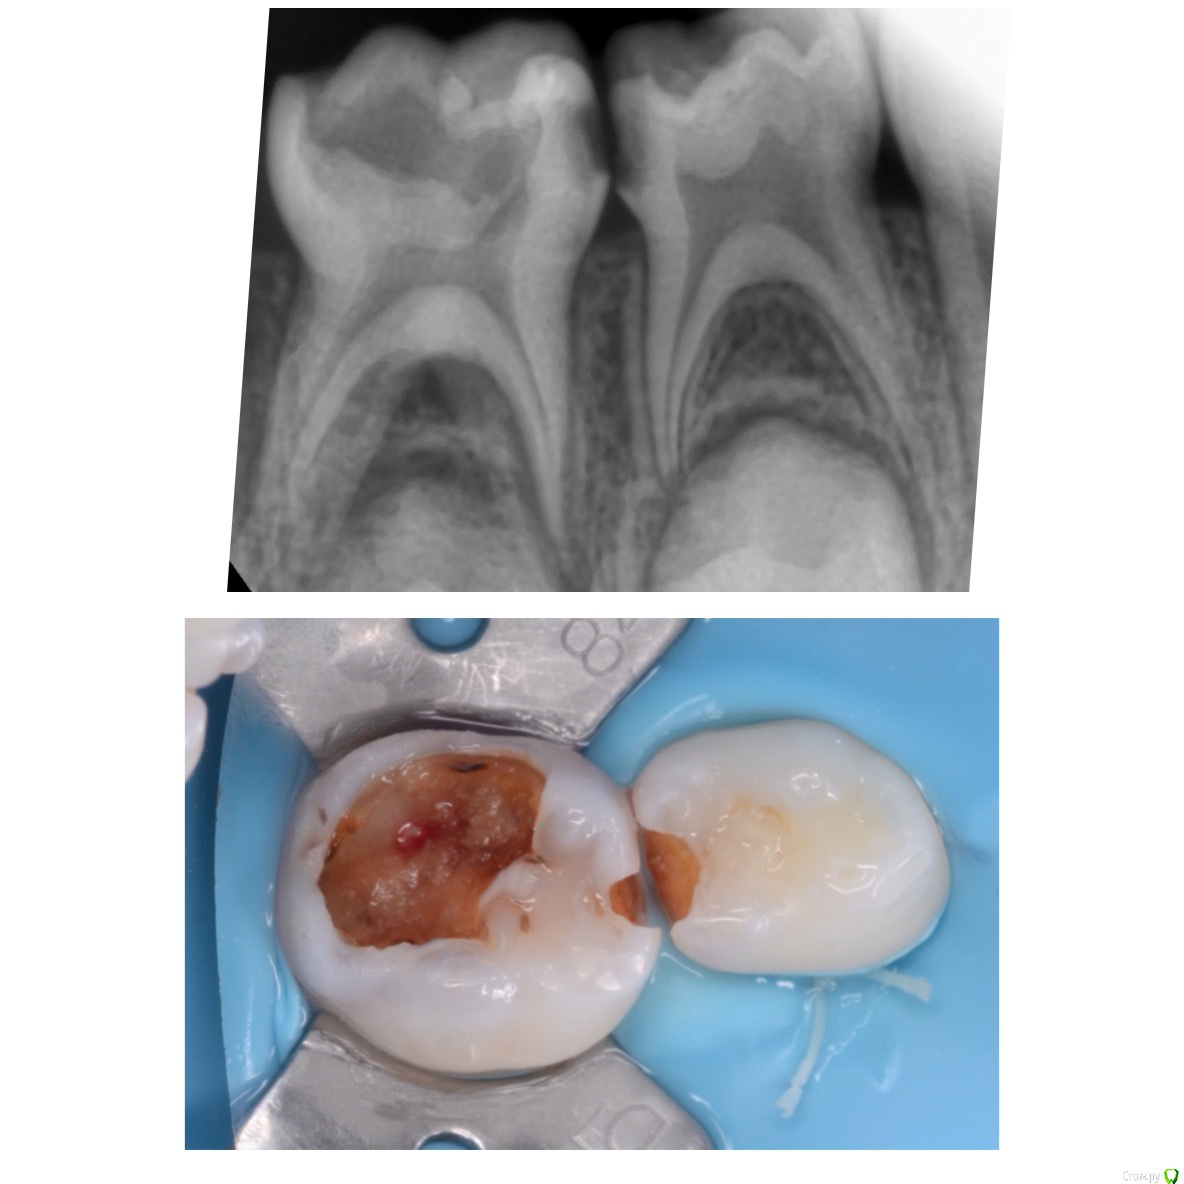

CRAZYDUCK Опубликовано 20 июня, 2018 Автор Поделиться Опубликовано 20 июня, 2018 Мысли вслух Отношение к периодонтитам у меня радикальное . Не было у меня положительных наблюдений. Девочке 4 года , лечение предстоит сложное и длительное . 8.5 зуб разница между первым фото и вторым почти три недели , точка вскрытия указана стрелкой . На момент лечения зуб болит , подвижен. Попытка лечения предпринята - экссудация из корневых каналов бешеная. Удалишь - нужно обязательно сделать распорку ( предотвратить медиальное смещение 6), но можно легко пропустить момент прорезывания 6 и он быстро встанет на место удалённого 8.5. Предпринять попытку лечения - 50/50 успех , заменить кальций даст ребёнок в 4 года .? В общем нет одного решения для всех похожих клинических ситуаций . 84 лечение обратимого пульпита , 8.5 удаление . 1 Ссылка на комментарий

crown Опубликовано 20 июня, 2018 Поделиться Опубликовано 20 июня, 2018 Я не очень понял, что было сделано с зубом 8.5? Вылечить его реально, периодонтиты у детей заживают очень быстро, быстрее чем у взрослых. Только вот возраст это да это проблема, в 4 года лечить очень тяжело. Ссылка на комментарий

CRAZYDUCK Опубликовано 21 июня, 2018 Автор Поделиться Опубликовано 21 июня, 2018 Я не очень понял, что было сделано с зубом 8.5? Вылечить его реально, периодонтиты у детей заживают очень быстро, быстрее чем у взрослых. Только вот возраст это да это проблема, в 4 года лечить очень тяжело. а я и не написала , что делала -экстирпация , обработка каналов Гх , в такой ситуации начинаю с 5 зуба . Если экссудации из корневых каналов нет ( после мед обработки Каналов), то лечим -кальций в каналах с последующей заменой . Все время пока я лечила 8.4 ( вит ампутацией ) полость 85 быстро заполнилась кровью - это минут 20-30), успех лечения можно ожидать . Все зависит от того , что считать успехом . Несколько лет назад я пробовала лечить периодонтиты , с последующим контролем rvg .максимум год , бывало , что внешне ( состояние десны) было хорошо, а на снимке -резорбция, бывало , что свищи появлялись все равно . Все снимки я не могу показать ( остались на прежней работе и фото я тогда не делала ). Для меня важный критерий- защита зачатка . Есть сомнения во временном - лучше удалить . 1 Ссылка на комментарий